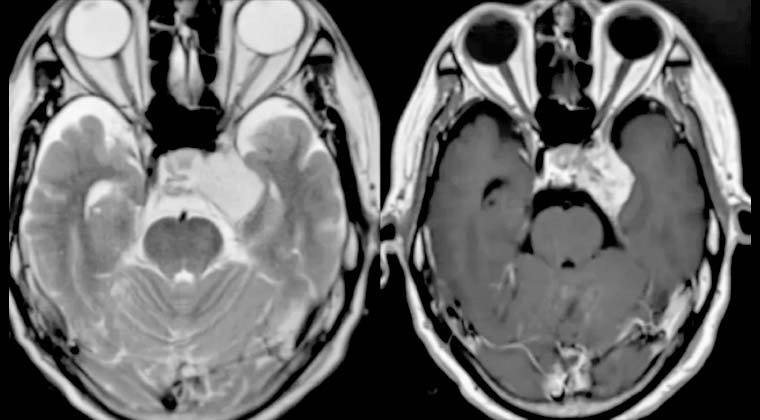

③ Случай 3:

Пациент: мужчина, 65 лет

Кавернозная гемангиома кавернозного синуса

Рисунок 1: 10.06.2020 Планирование лечения Гамма-ножом

Рисунок 2: 06.01.2021, через 6 месяцев после лечения Гамма-ножом очаг значительно уменьшился